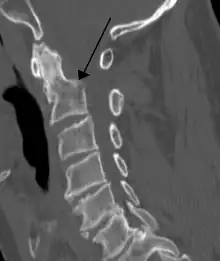

A fracture of the base of the dens as seen on CT